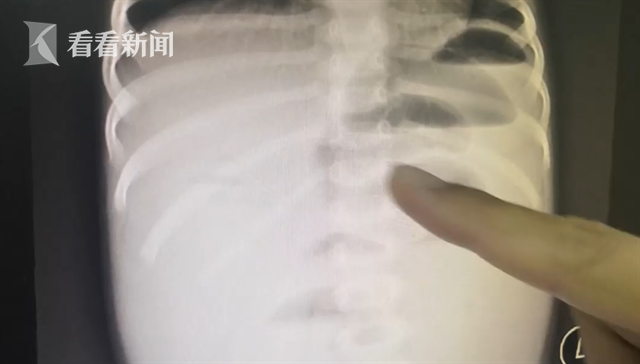

深圳市儿童医院普外一科医生储冬冬说:“可以看到她出现了一个很明显的肠梗阻,就是上面的肠子扩张得很明显,底下的肠子已经完全没有气了,就是一个空扁的状态。这个就是提示我们她的肠梗阻很严重,有急诊手术的体征。消化道里面有一个异物是球形的。已经把肠子完全塞住了。”